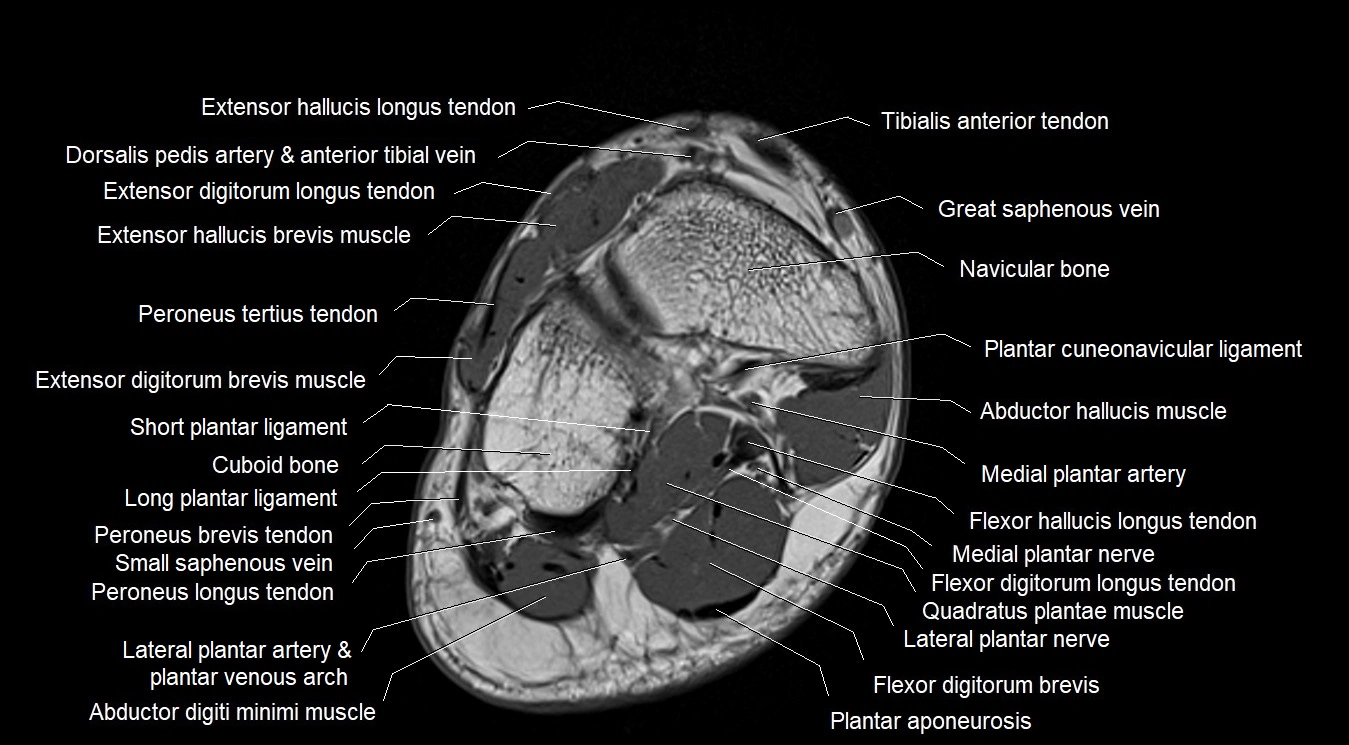

The abductor digiti minimi (ADM) is a superficial intrinsic muscle of the sole of the foot, located along the lateral border. It forms the most medial muscle of the lateral plantar compartment. The ADM abducts and flexes the fifth toe (little toe) at the metatarsophalangeal joint and provides lateral stability to the foot during gait.

It is clinically relevant in plantar fasciitis, heel pain syndromes, and nerve entrapments such as Baxter’s neuropathy, which affects the first branch of the lateral plantar nerve.

Origin: Medial and lateral processes of the calcaneal tuberosity, plantar aponeurosis, and intermuscular septum

Insertion: Lateral aspect of the base of the proximal phalanx of the 5th toe; sometimes attaches to the tendon of the flexor digiti minimi brevis

Deep: Flexor digitorum brevis, quadratus plantae, lateral plantar vessels and nerve

Lateral plantar nerve (first branch), from tibial nerve (S1–S3)

Lateral plantar artery, branch of posterior tibial artery